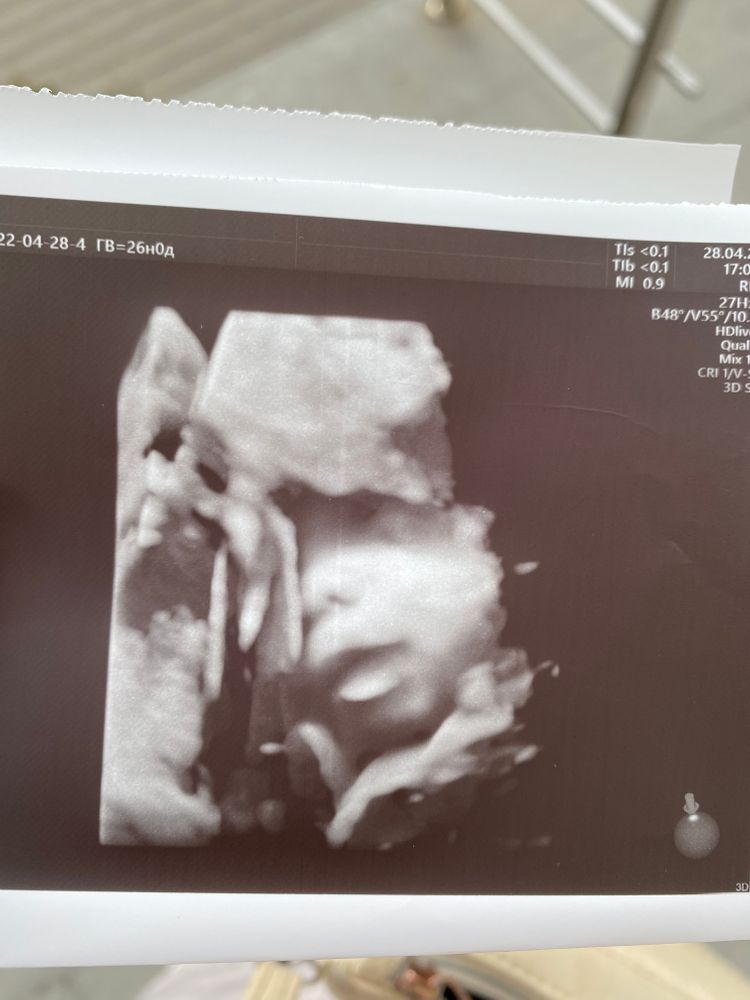

Тонус. 3D узи.